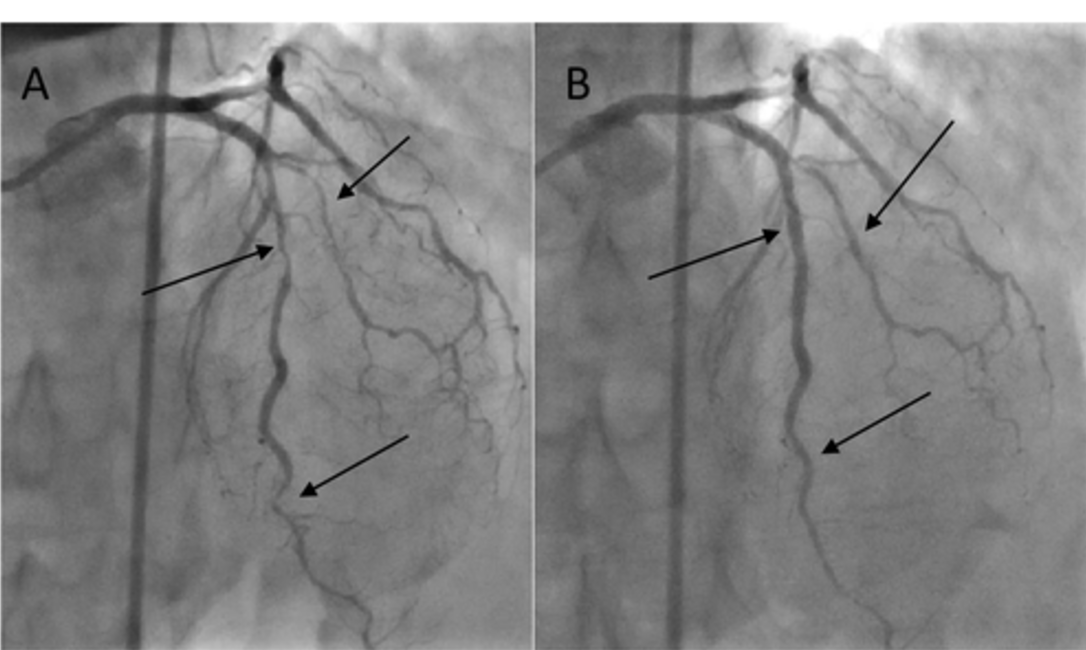

干预前两天,停用二甲双胍治疗,而雷米普利剂量减半至2.5mg。用40 mL低渗碘对比剂(碘普罗胺)进行冠状动脉造影,发现有两支冠状动脉病变。在左前降支(LAD)内侧段检测到 90%-99%的钙化狭窄,在远端段检测到90%狭窄,在第一对角支中检测到90%-99%狭窄。在右冠状动脉 (RCA) 中观察到两个主要狭窄:近端段为 70%-90%,内侧段为90%-99%。患者不同意手术血运重建,因此计划进行经皮冠状动脉介入治疗 (PCI)。四天后,在适当补液后进行 PCI,在 LAD 中植入两个药物洗脱支架,并对第一对角分支进行球囊血管成形术(图 1)。此外,三个裸金属支架植入 RCA(图 2)。考虑到手术的复杂性,使用了225 mL低渗碘对比剂,然后充分补液。然而,尽管采取了这些预防措施,干预后 36小时肾功能恶化,血尿素氮(15.7mmol/L)和血清肌酐(从150-227μmol/L)升高,但仍持续利尿。

图1